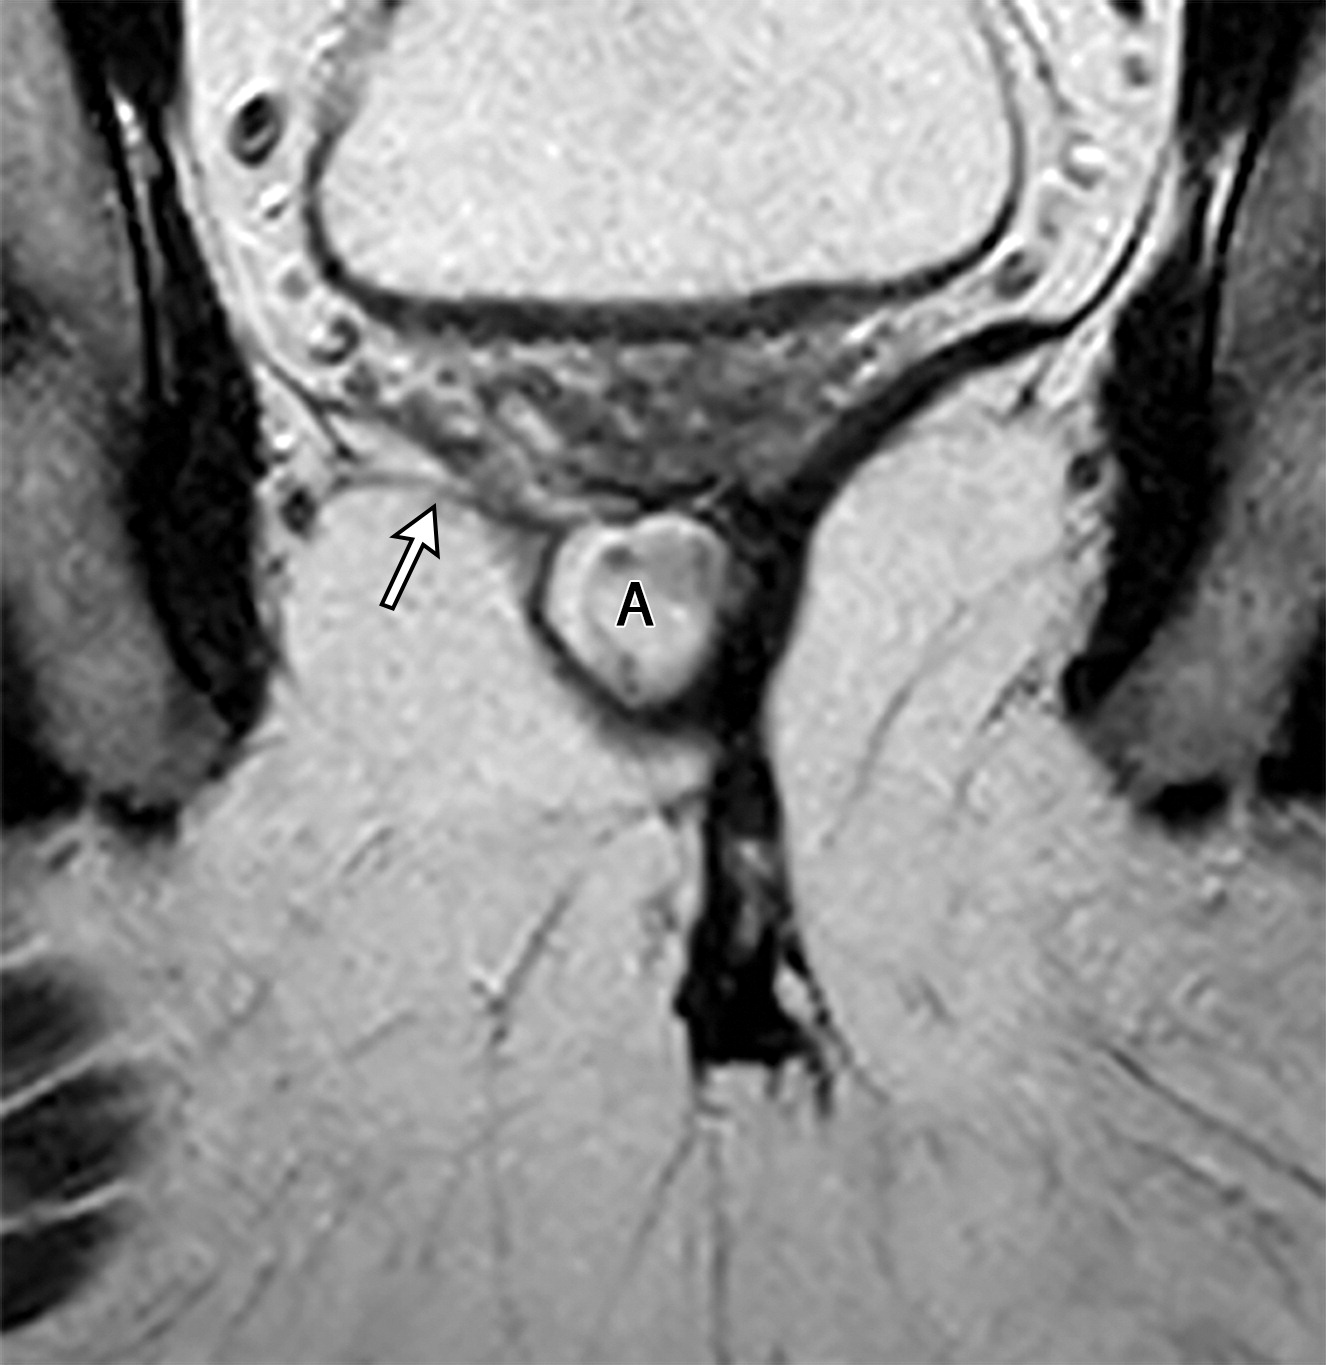

1327c40cd0748e6d87b4cfea2fce8541.jpeg5e035c7e4059e08fb1d03d282633f38e.jpeg髂尾肌的不同形态。

(上图)右侧髂尾肌萎缩(上图白色长箭头),复发性直肠腺癌(上图黑色字母A),(下图)另一个患者,双侧髂尾肌增厚(下图黑色短箭头)。